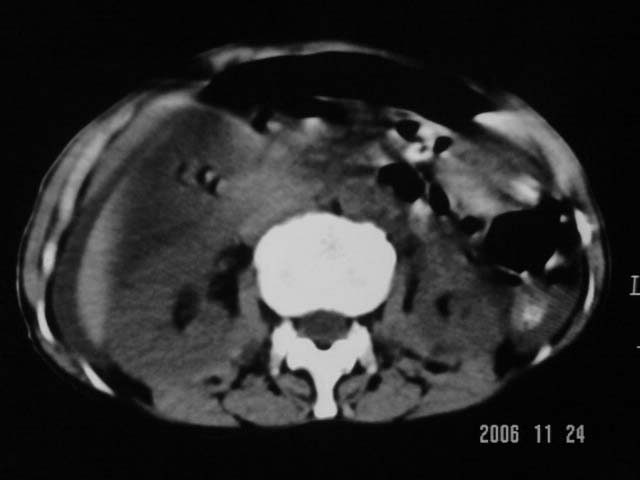

仰卧位见:肝前间隙及肝脾间隙内可见新月形气体密度影,边缘清楚,侧卧位见气体随体位改变而移动,ct值约-929hu。膈下、肝下间隙及部分肠间隙可见液性密度影。考虑:1、上腹部空腔脏器穿孔,以胃穿孔可能性大。2、少量腹水。

仰卧位见:肝前间隙及肝脾间隙内可见新月形气体密度影,边缘清楚,侧卧位见气体随体位改变而移动,ct值约-929hu。膈下、肝下间隙及部分肠间隙可见液性密度影。考虑:1、上腹部空腔脏器穿孔,结合临床,首先考虑胃穿孔可能性大。2、少量腹水

补充--肝门及肝肾间隙以见积气显示。

支持消化道空腔脏器穿孔(腹腔内大量游离气体影,小网膜囊内亦见气体影),少量腹水。